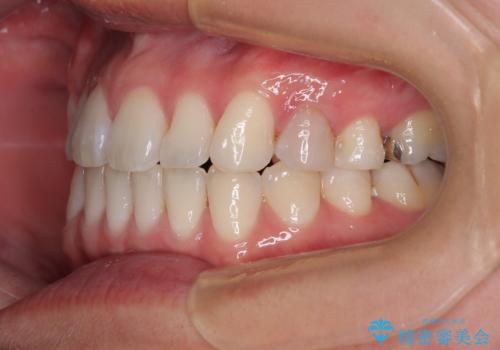

マウスピース矯正が煩わしい ワイヤー装置での非抜歯矯正

上下前歯のデコボコを気にして来院された患者様です。

ワイヤー矯正でもマウスピース矯正でも可能でしたが、短期間で、自身の手を煩わせることなく治療を行いたいとのことで、ワイヤー装置にて矯正治療を行うこととしました。

舌の突出癖により、治療過程でスペースが多くできましたが、舌のトレーニングを頑張っていただき、1年強で終えることができました。